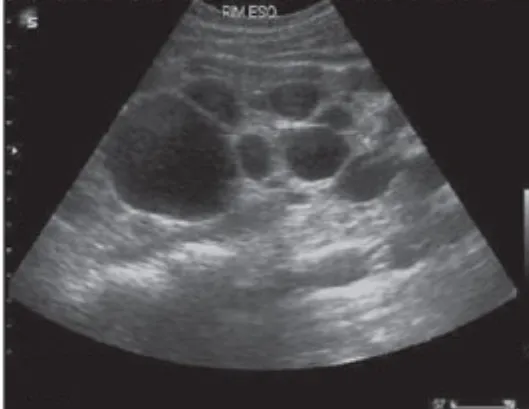

A DRPAD não é contraindicação à DP — e, na prática, muitos pacientes têm resultados comparáveis à hemodiálise. O “porém” está na mecânica: rins/hepatomegalia podem reduzir tolerância a volumes, aumentar risco de hérnias e extravasamentos, e piorar desconforto respiratório. Com técnica adequada (cateter presternal ou lateral, volumes menores, cicladora noturna e decúbito supino), a maioria das barreiras é contornável. Neste post, revisamos quando a DP é ótima, quando exigir cautela e como ajustar a prescrição para segurança e qualidade de vida.

Uso do Tolvaptan na Doença Renal policística, dicas de prescrição!

Tolvaptan é um medicamento indicado para retardar a progressão da doença renal policística autossômica dominante (DRPAD). Ele age reduzindo o crescimento dos cistos renais e requer monitoramento regular devido a possíveis efeitos adversos, como hepatotoxicidade e desidratação. Sua prescrição é indicada para pacientes com alto risco de progressão da doença. Confere aqui as dicas práticas de prescrição e seguimento.